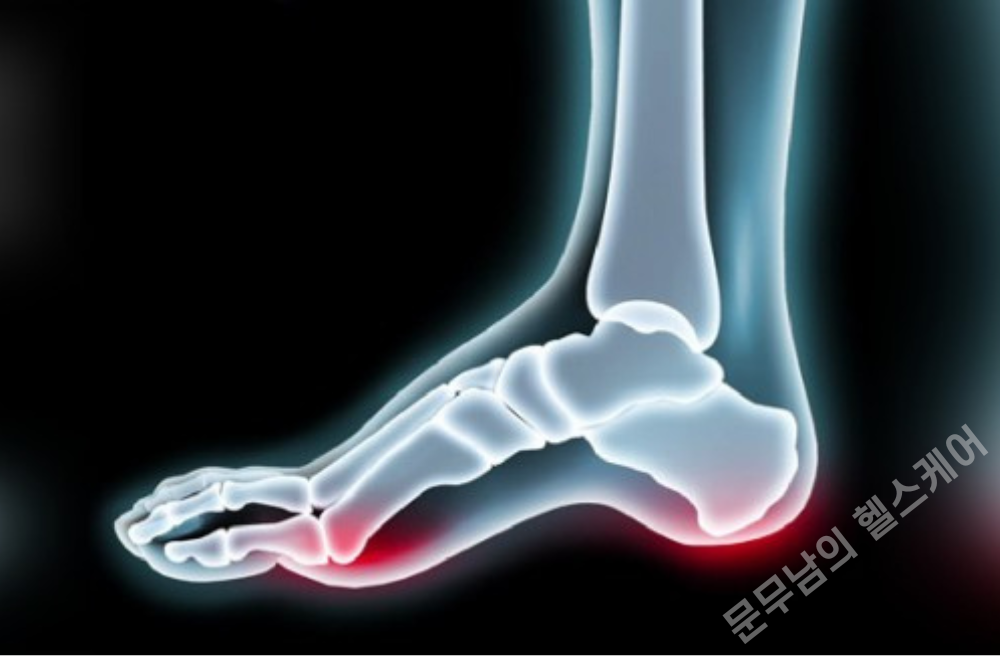

요족이라는 것은 기본적으로 발등이 정상보다 높이 올라와 있는 상태를 의미합니다. 옆에서 보았을 때는 발바닥의 아치가 높아서 발바닥이 위로 오목하게 올라간 것처럼 보이곤 하지요.

이런식으로 지나치게 높은 아치발 형태는, 체중이 발바닥 전체에 골고루 분산되지 못하게 하여 체중이 발뒤꿈치나 앞꿈치 방향으로 쏠리게 합니다. 이러한 상태는 곧 여러가지 근골격계 질환들을 유발하게 됩니다.